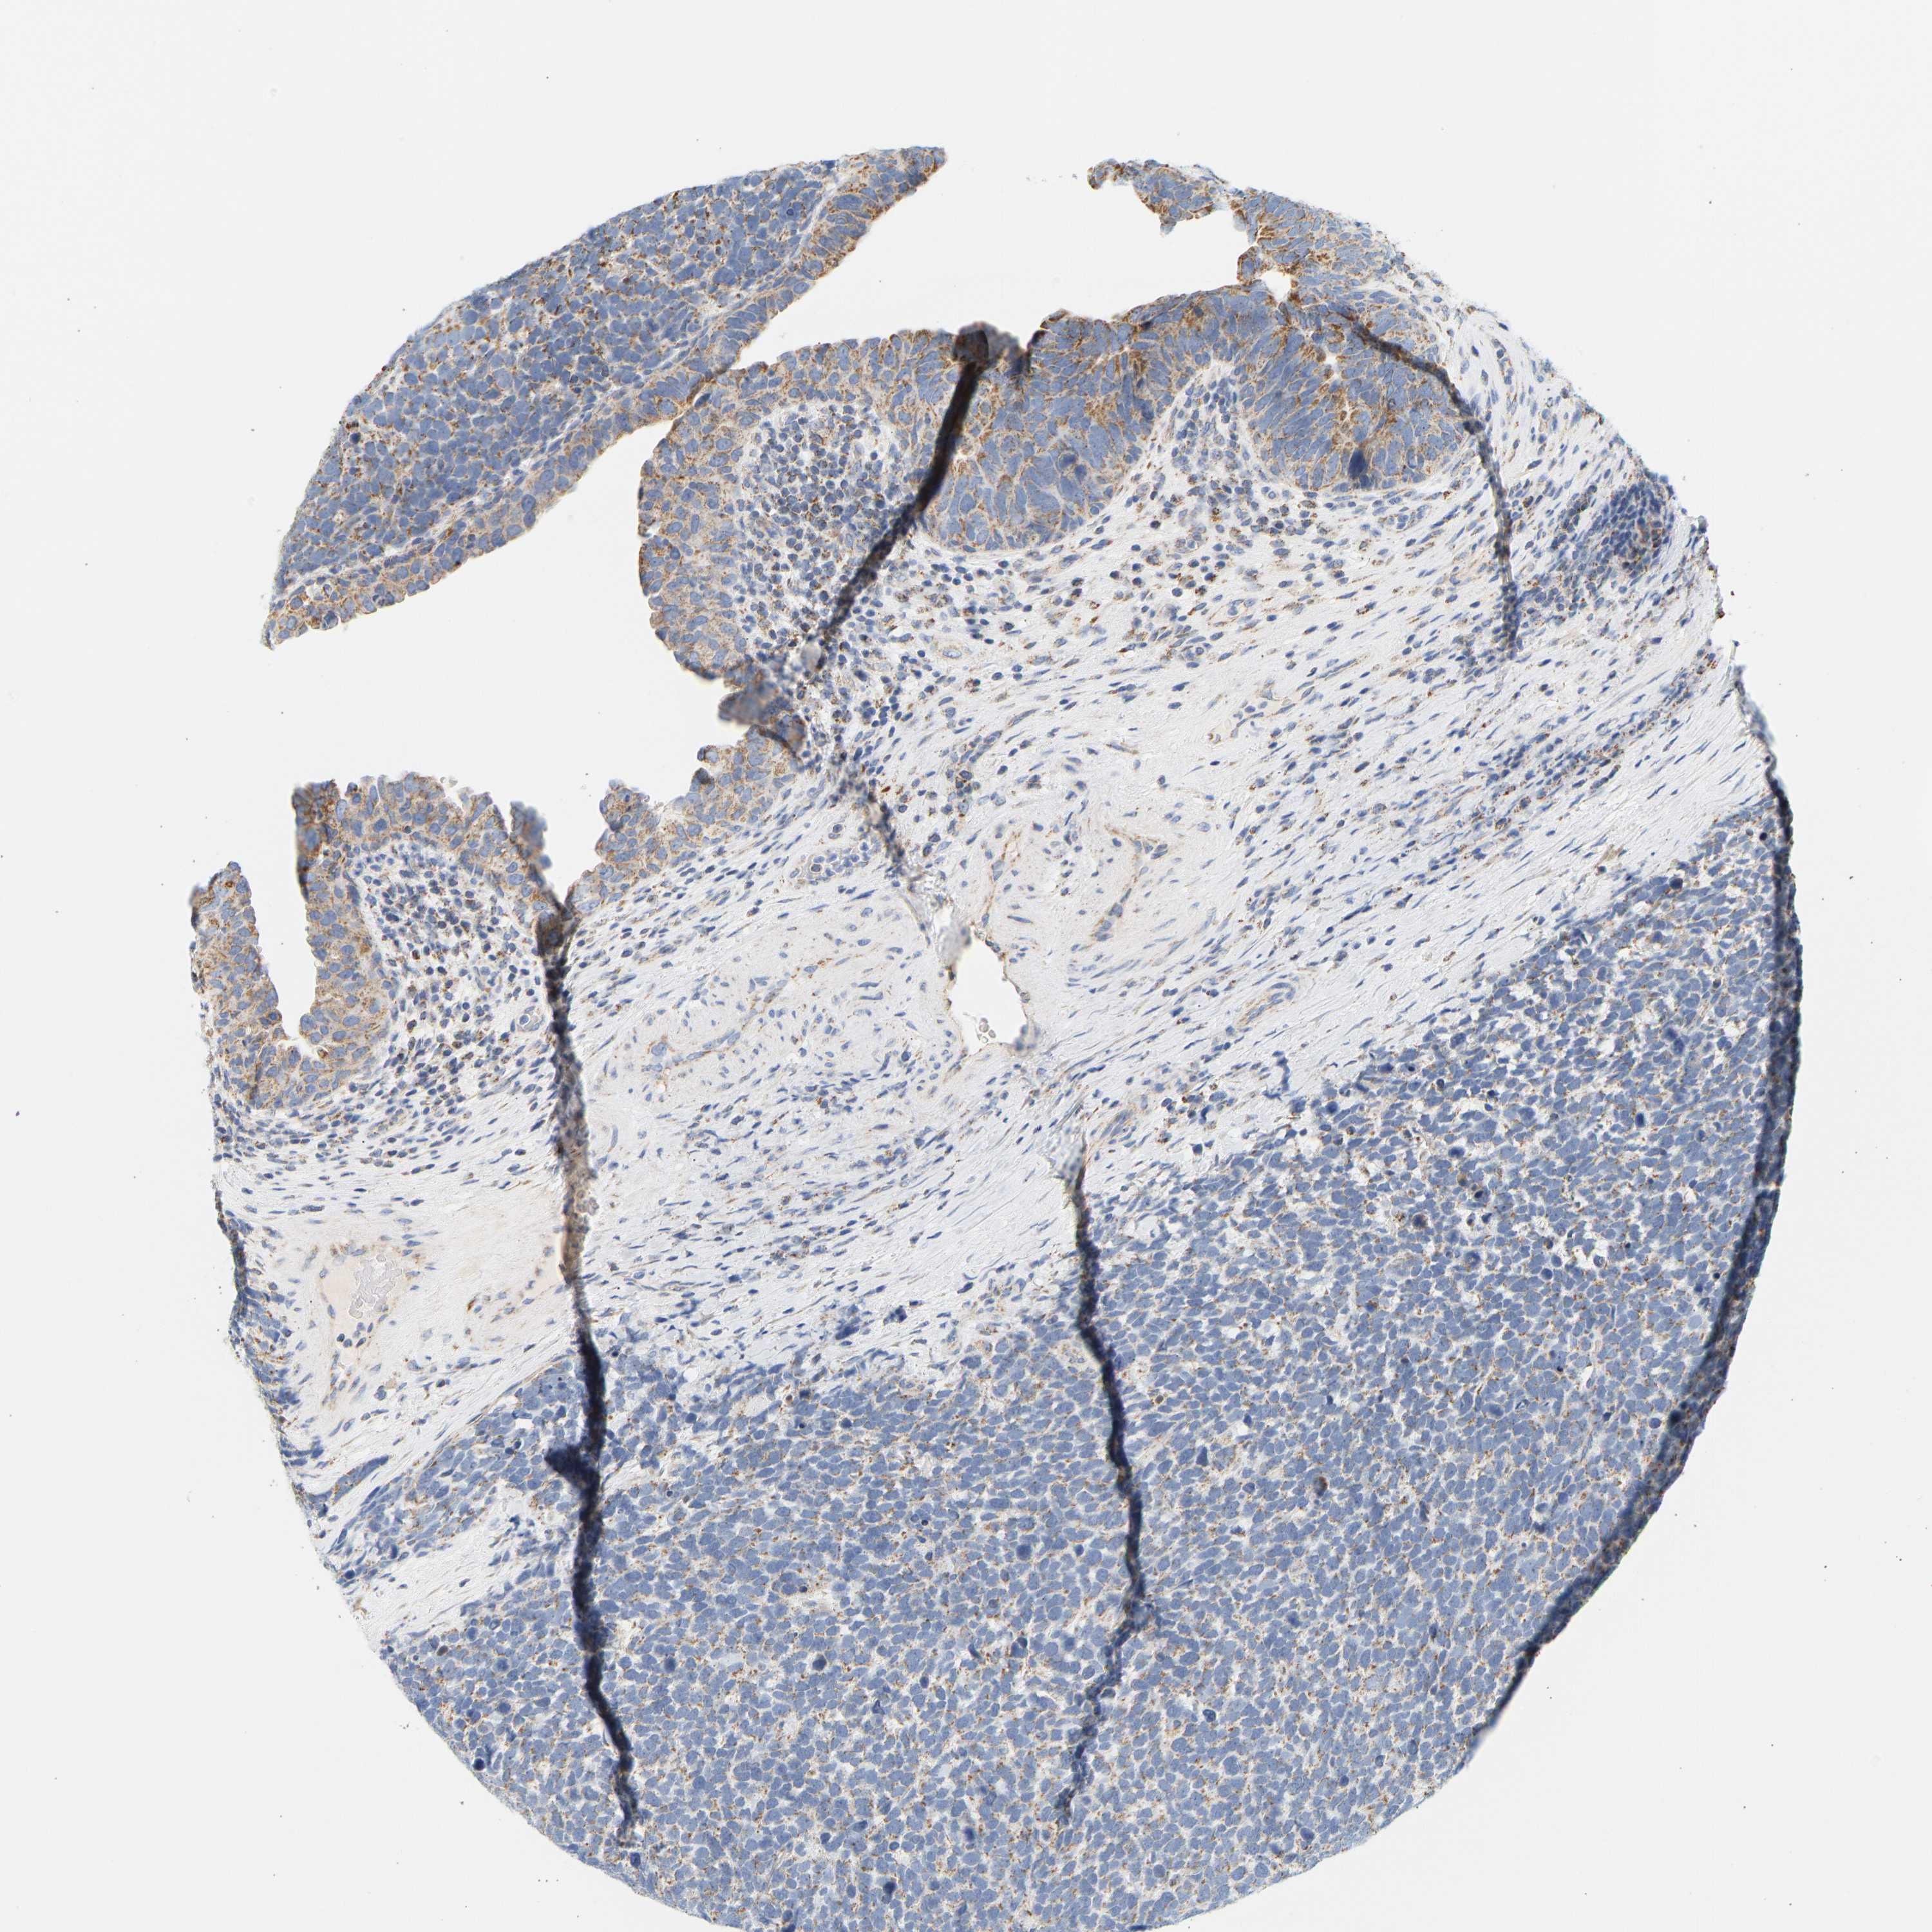

UROTHELIAL CANCER - Protein expressioni

A mouse-over function shows sample information and annotation data. Click on an image to view it in a full screen mode. Samples can be filtered based on level of antibody staining by selecting one or several of the following categories: high, medium, low and not detected. The assay and annotation is described here.

Note that samples used for immunohistochemistry by the Human Protein Atlas do not correspond to samples in the TCGA dataset.

Antibody stainingi

Antibody staining in the annotated cell types in the current human tissue is reported as not detected, low, medium, or high, based on conventional immunohistochemistry profiling in selected tissues. This score is based on the combination of the staining intensity and fraction of stained cells.

Each image is clickable and will lead to virtual microscopy that enables deeper exploration of all samples and also displays staining intensity scores, fraction scores and subcellular localization as well as patient and tissue information for each sample.

Antibody HPA018173

Antibody HPA023211

Staining

High

Medium

Low

Not detected

Intensity

Strong

Moderate

Weak

Negative

Quantity

>75%

75%-25%

<25%

None

Location

Nuclear

Cytoplasmic/membranous

Cytoplasmic/membranous,nuclear

Urothelial carcinoma, Low grade

Urothelial carcinoma, High grade